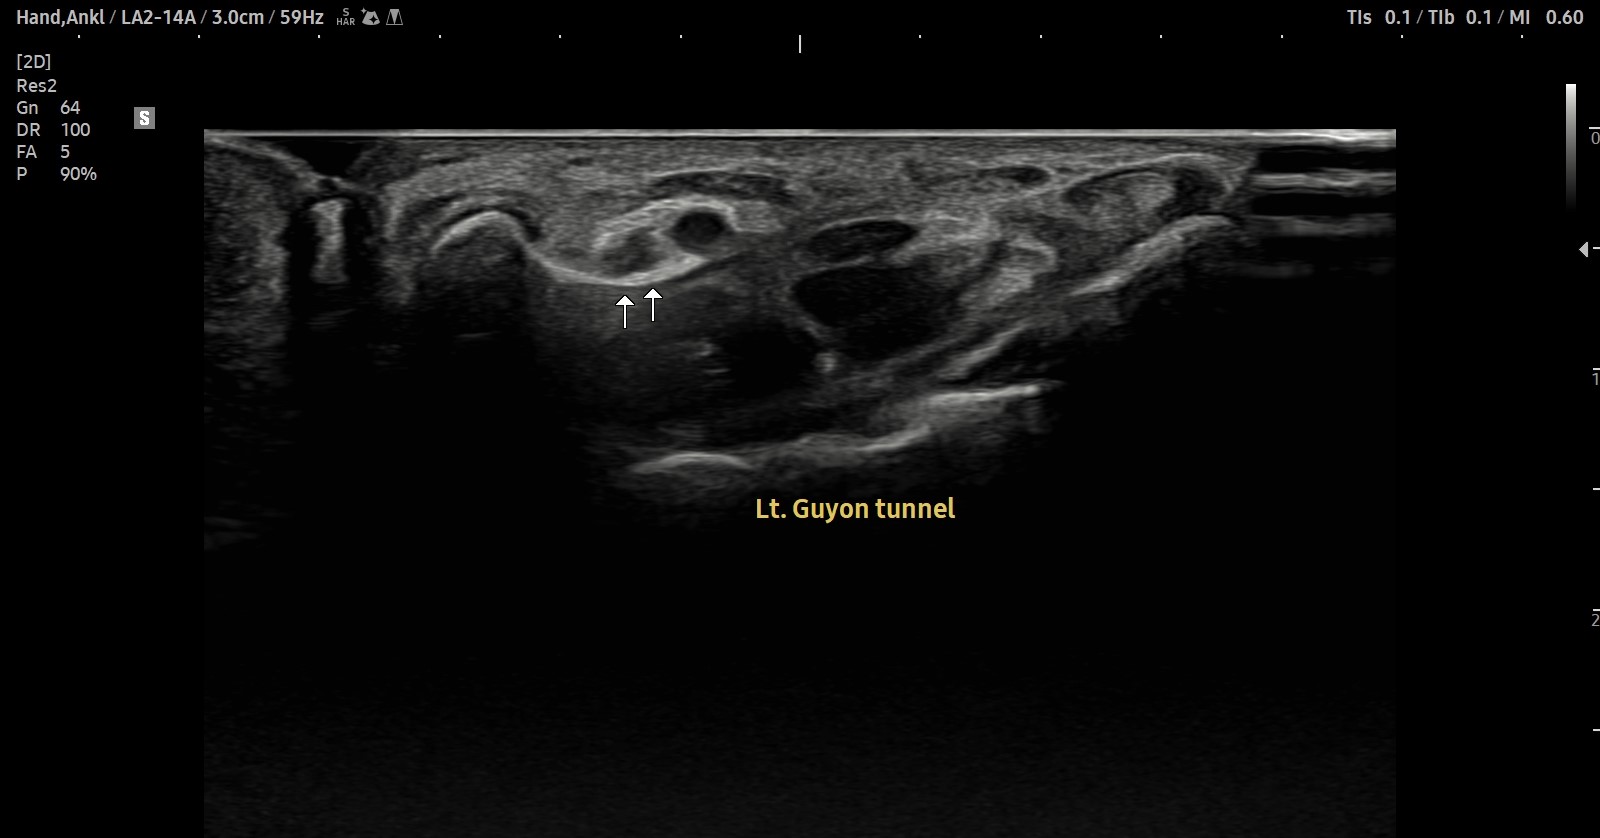

- 치료기간 : 25 . 8 .19 ~ 25 . 11 . 20

- 치료횟수 : 25 회 (사이클 치료 3 +아피톡신 10회)

치료 전

치료 후

좌측 골프엘보 : 12/2

좌측테니스엘보: 12/8

우측 골프엘보 : 12/2

우측 테니스엘보: 12/8